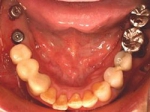

片側2歯欠損片側2歯欠損片側2歯欠損 主訴-入れ歯を使ってみたが違和感強くてダメ。固定のものにしたい。術前下顎口腔内(鏡像) 二次オペ時(鏡像)二次オペ時(鏡像)二次オペ時(鏡像) 術後術後術後、左下奥2本インプラント(鏡像) 術後(レントゲン)術後(レントゲン)術後(レントゲン)、左下奥2本インプラント